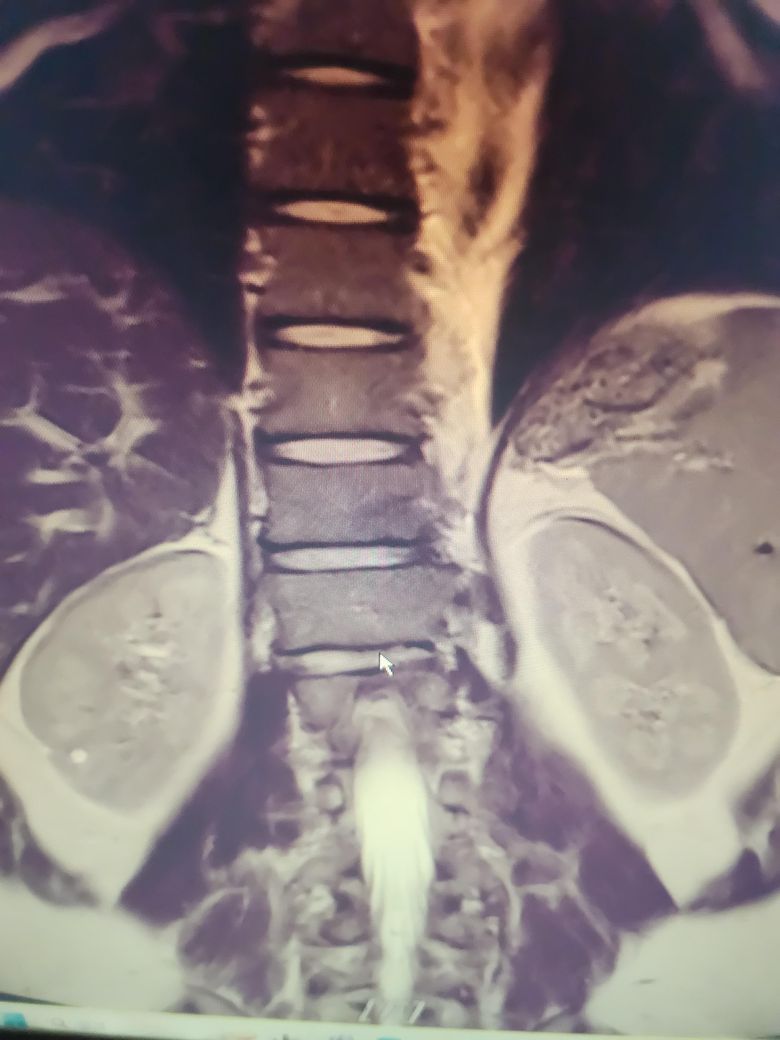

mri 촬영 오른쪽 신장물혹 0.5cm 혹시 하얀색 점같은거 저거맞을까요?? 사진첨부해봅니다

비조영으로 췌장검진목적으로 촬영했는데 뜬금없이 신장에 물혹 작은게 하나있다고 씨디 가져와서 제가직접보니 대충 저건거같은데 혹시 맞을까요?? 단순낭종이라고 하시더라구요

혹시 나중에 시간지나서 커질수있는지... 지금제거하고싶은데 콩팥밖으로 자라있어서 제거가능하지않을까요??